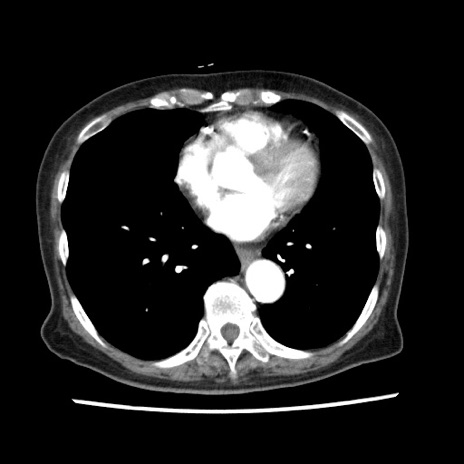

矢状断像

【症例】80歳代女性

【主訴】腹痛

【現病歴】8時間前から腹痛あり来院。

【既往歴】糖尿病、脂質異常症、子宮体癌にて子宮全摘術

【身体所見】意識清明・会話良好だが腹痛で苦悶様、全腹部にわたって反跳痛と圧痛あり

【データ】WBC 13600、CRP 0.14、LDH 224、CK 90